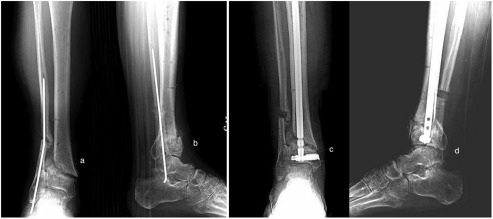

The patients were followed up for 3 years (Fig. 5 a and b), 3 months (Fig. 6 a and b), and 6 months (Fig. 7 a and b), respectively. Osteotomies were performed on Patient 1 and Patient 2; nonunion experienced by Patient 3 healed radiologically and clinically within 6 weeks postoperatively. American Orthopaedic Foot and Ankle Society scores were 36, 33, and 21 preoperatively; and 75, 68, and 75 postoperatively in Patients 1, 2 and 3, respectively (Fig. 8 a–d). There was neither propagation of nails into the ankle joint nor implant failure.

Fig. 5.

Final follow-up (postoperative 3 years) AP (a) and lateral (b) X-rays of Patient 1.

Fig. 6.

Final follow-up (postoperative 3 years) AP (a) and lateral (b) X-rays of Patient 2.

Fig. 7.

Early postoperative AP (a) and lateral (b) and final follow-up (postoperative 3 years) AP (c) and lateral (d) X-rays of Patient 3.